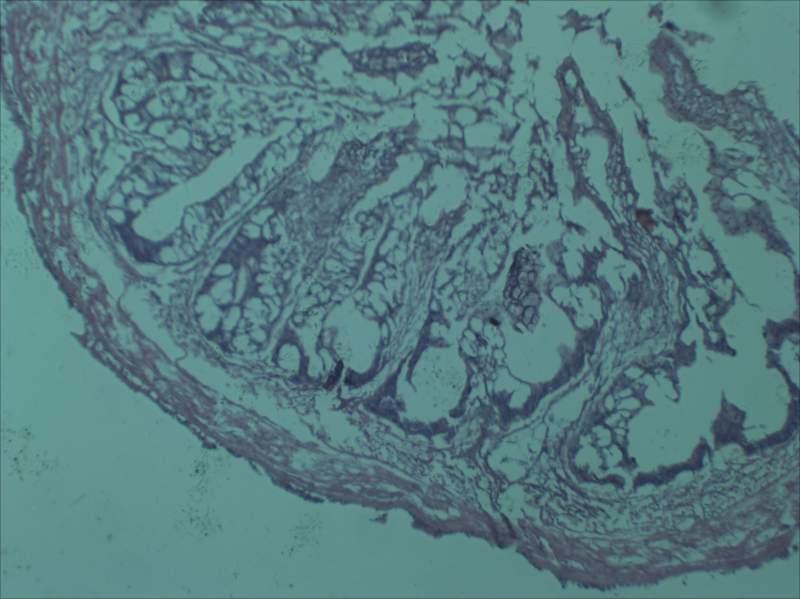

µÚ¶þÕÅÊǽñÄê×öµÄ³¦µÀÇÐÆ¬£¬È¾É«ÊÇÕâ¸öÑù×Ó£¬Ôõô¿´¶¼²»¶Ô£¬´óÖ¿ÉÒÔ¿´³ö³¦µÀµÄ½á¹¹£¬µ«Êǵ½´¦¶¼ÊÇ¿ÕÅÝ£¬²»Ã÷°×µ½µ×ÊÇʲôÇé¿ö¡£

µÚÈýÕÅÊǽñÄê×öµÄ¸ÎÔàÇÐÆ¬£¬È¾É«Ò²ÊÇÕâ¸öÑù×Ó¡£